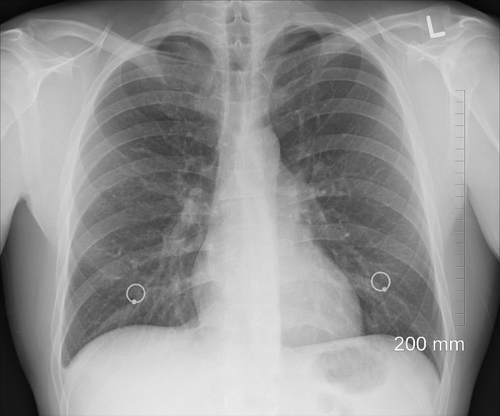

폐렴은 바이러스나 세균에 의해 세기관지 이하 폐 조직에 염증이 생기는 감염성 질환입니다. 기침, 가래, 발열과 같은 증상이 일반적이고 흉부 X-ray 사진으로 폐렴 의심 소견을 확인할 수 있습니다.